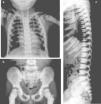

Presentation of the CaseA 4-year old male with a history of blindness in relation to congenital optic neuropathy of non-filiation aetiology and delayed growth. He presented at the emergency department after low intensity trauma in the right leg. An X-ray was taken which showed a fracture in the distal shaft of the tibia and fibula, together with a fracture callus in the proximal third of the fibula and general sclerosis of the visible bony structures which indicated sclerosing bone dysplasia (Fig. 1). The radiologic study was completed with a bone series, where a diffuse increase in bone density was highlighted with a “bone within bone” appearance and the enlargement of long bone metaphysis (Figs. 2–4). Radiologic findings determined the diagnosis of osteopetrosis.

X-rays of the chest (a) and pelvis (b) show a diffuse and homogenous increase in bone density, more obvious in costal arcs and pelvic bones, also poor cortico-medullary differentiation and enlargement of long bone metaphysis. In the lateral projection of the spine (c), we observe sclerosis of the upper and lower plates of the vertebral bodies, in an image called a sandwich vertebral body.